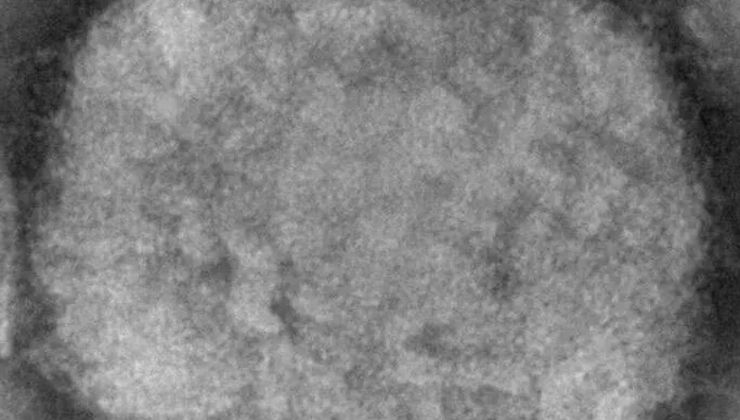

Maymun çiçeği virüsü ilk olarak 4 Mayıs tarihinde Londra’da görülürken, üzerinden kısa bir zaman geçmesine rağmen 30 ülkeye yayılarak küresel bir salgın haline geldi. Temmuz ayında ise 6 kıtada 70’den fazla ülkeye yayılırken, Dünya Sağlık Örgütü 21 Temmuz itibarıyla maymun çiçeği salgınıyla alakalı ‘küresel acil durum’ ilan etti. Türkiye’de ise ilk vaka 30 Haziran tarihinde ortaya çıkarken, Türkiye’de görülen toplam vaka sayısının 5’e yükseldiği açıklandı.

Dünya’da görülen toplam vaka sayısı ise 24 bin 381 olarak görülürken, çoğunlukta olan ülkeler; Almanya, ABD, Brezilya, İspanya ve Fransa olarak kayıtlara geçti.